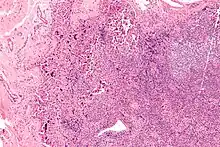

| Lymphadenopathy due to systemic lupus erythematosus with characteristic necrosis and haematoxylin bodies. H&E stain. | |